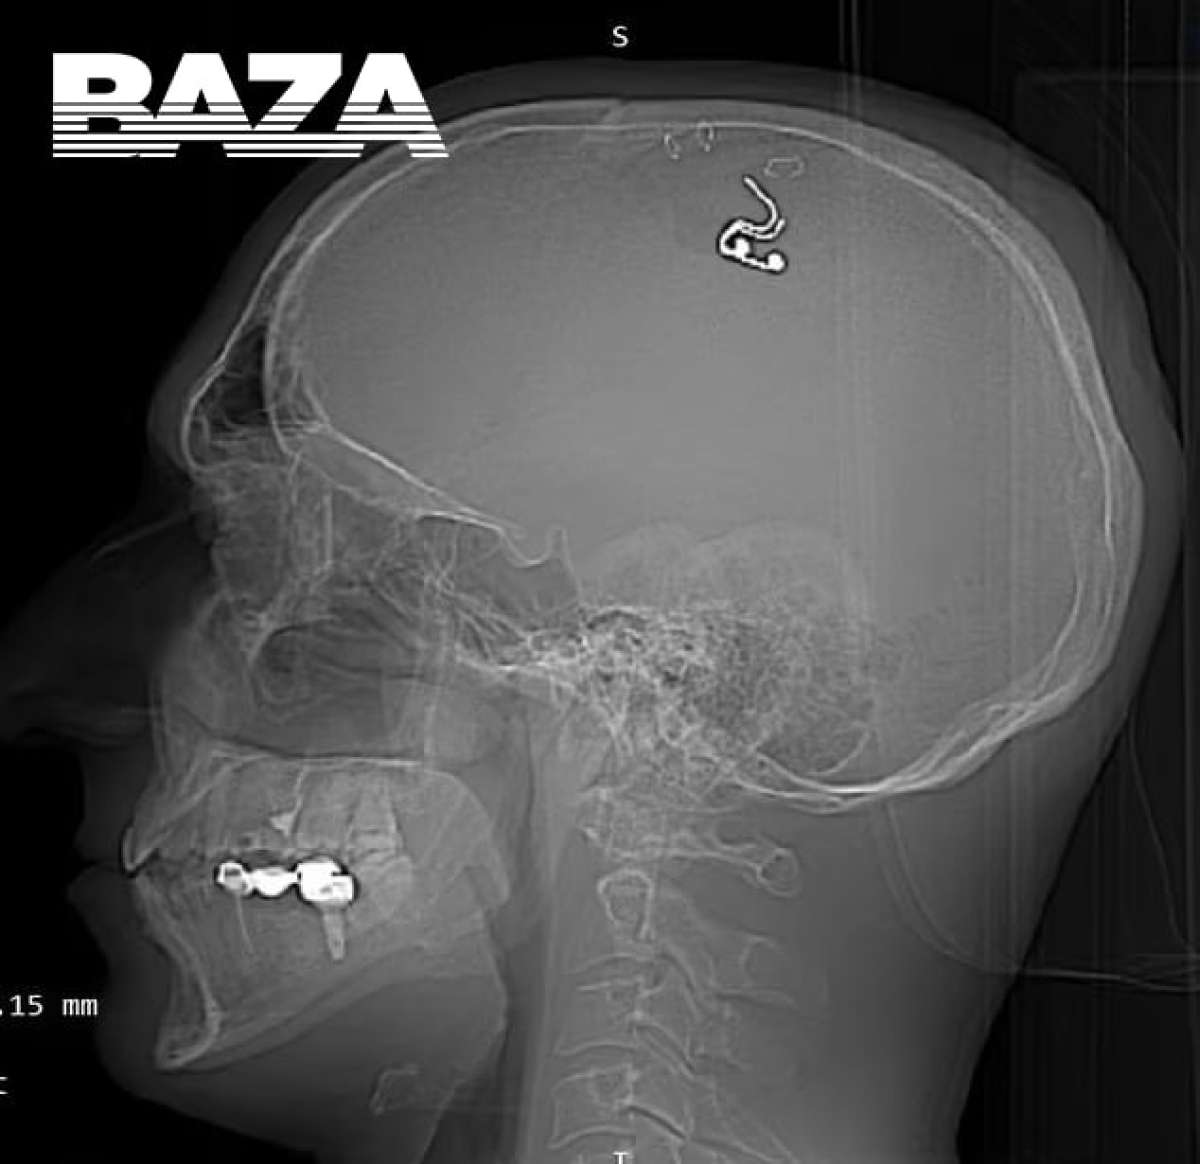

FOTO: Sam si je s svedrom odprl lobanjo in čipiral možgane, da bi lažje nadzoroval sanje

40-letni Mikhail Raduga trepanacijo opravil kar doma v dnevni sobi, in sicer v Almatiju v Kazakhstanu, kamor se je pred kratkim preselil. Za to je ure in ure preučeval videoposnetke na spletu o delu nevrokirurgov in celo vadil na petih ovcah. V trgovini je nabavil električni vrtalnik in se lotil posla. Ko si je s svedrom odprl lobanjo, je vsadil elektrodo v možgane, skalp pa potem pritrdil nazaj s sponkami za papir.

Vse to je 40-letnik kot rečeno opravil z namenom, da mu bo elektroda s stimulacijo motorične skorje možganov pomagala nadzorovati sanje. Menda se je s to tematiko ukvarjal že dolgo in se je za vgradnjo vsadka nameraval obrniti na uradno kirurgijo, kar pa mu zaradi kriminalne preteklosti ni uspelo. Uradna medicina je nad podvigom zgrožena; med posegom bi ga lahko zadela kap, zdaj pa je v nevarnosti, da razvije epilepsijo.